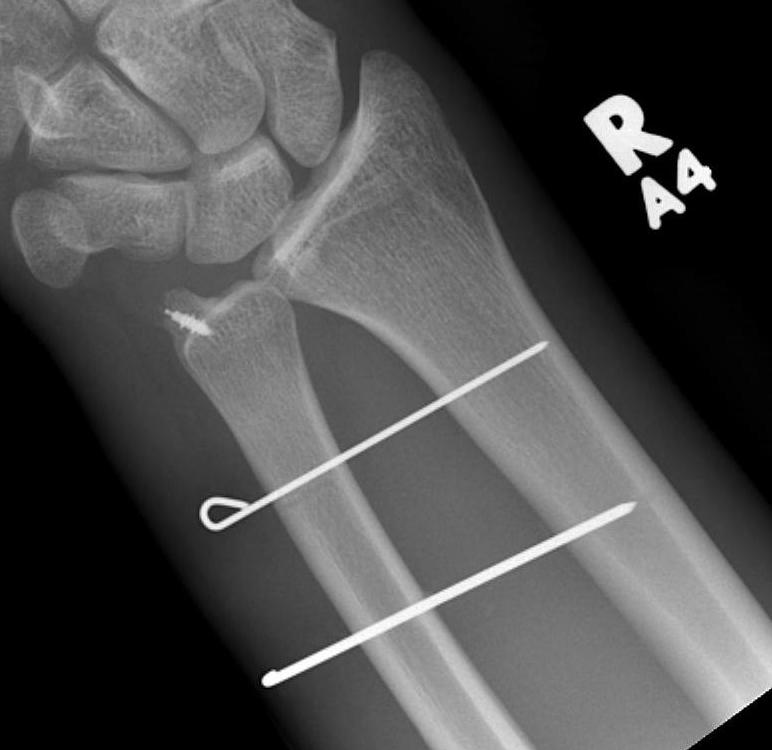

Galeazzi fracture

Galeazzi fracture with DRUJ disruption

Incidence of DRUJ instability after radius ORIF

Rettig et al J Hand Surg Am 2001

- 40 patients with Galeazzi fracture dislocations

- DRUJ instability after radius ORIF

- Type 1: radius fracture < 7.5 cm to articular surface: 55% DRUJ instability

- TYpe II: radius fracture > 7.5 cm to articular surface: 6% DRUJ instability